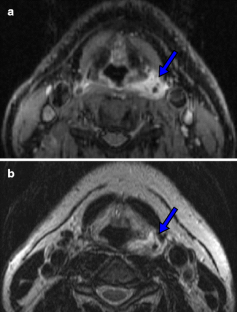

The aim of the study was to determine objective radiological signs of danger to life in survivors of manual strangulation and to establish a radiological scoring system for the differentiation between life-threatening and non-life-threatening strangulation by dividing the cross section of the neck into three zones (superficial, middle and deep zone). Forensic pathologists classified 56 survivors of strangulation into life-threatening and non-life-threatening cases by history and clinical examination alone, and two blinded radiologists evaluated the MRIs of the neck. In 15 cases, strangulation was life-threatening (27%), compared with 41 cases in which strangulation was non-life-threatening (73%). The best radiological signs on MRI to differentiate between the two groups were intramuscular haemorrhage/oedema, swelling of platysma and intracutaneous bleeding (all p = 0.02) followed by subcutaneous bleeding (p = 0.034) and haemorrhagic lymph nodes (p = 0.04), all indicating life-threatening strangulation. The radiological scoring system showed a sensitivity and specificity of ≈70% for life-threatening strangulation, when at least two neck zones were affected. MRI is not only helpful in assessing the severity of strangulation, but is also an excellent documentation tool that is even admissible in court.